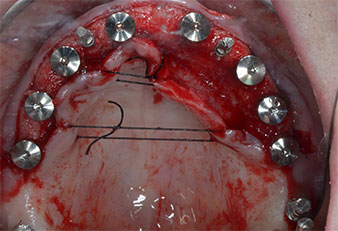

Trois ans après, le moment était venu pour elle de se doter d’une prothèse maxillaire du même type. Sur la base de la planification CBCT, l’élévation sinusale a été évitée grâce à la pose d'implants courts, et un gabarit chirurgical a été utilisé pour transférer les positions planifiées sur la crête alvéolaire (Figures 1 et 2).

Un insert piézoélectrique diamanté de forme effilée (Piezomed I1) a été utilisé pour marquer les positions implantaires et effectuer la préparation pilote (Fig. 3). On a pris soin de travailler selon un mouvement ascendant et descendant, à puissance réduite, irrigation complète et basse pression (moins de 300g). Ensuite, un insert pilote (Piezomed I2A/I2P) a été utilisé pour l’agrandissement initial de 2mm du diamètre des sites implantaires (Fig. 4), suivi d’un insert de 3mm (Fig. 5).

Compte tenu de la dureté relative de l’os (D2) à cet endroit, les sites recevant des implants de 10mm de long aux régions 11 et 21 ont été finalisés à l'aide d’une fraise de 4mm de diamètre, associée à un contre-angle chirurgical W&H WS-75 L, au moteur d'implantologie Implantmed de W&H ainsi qu’au module Osstell ISQ de W&H. En revanche, en raison de leur structure osseuse molle, les sites postérieurs ont été préparés en vue de l’obtention d’un diamètre final de 3mm à l'aide de l’insert Piezomed I3P. Les implants ont enfin été posés par voie transgingivale (Flap Less) pour obtenir l’ostéointégration dans un délai de trois mois (Figures 6-10). L'appareil existant a été maintenu sur quatre implants provisoires (Fig. 8).